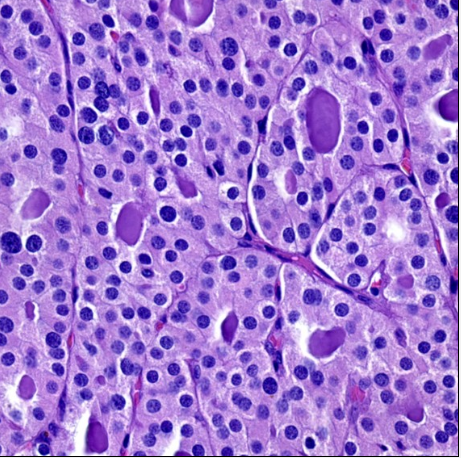

Phaochromocytoma

A “Zellballen” pattern is most common, consisting of nests of tumour cells separated by peripheral capillaries

Tumour cells resembling normal chromaffin cells that display basophilic to amphophilic cytoplasmic granularity. The cells here show mild nuclear pleomorphism and occasional nuclear pseudoinclusions, which can also be seen in adrenal cortical carcinomas. PAS(+) hyaline globules can be seen and nuclear pseudoinclusions. Can have pleomorphism but no mitoses